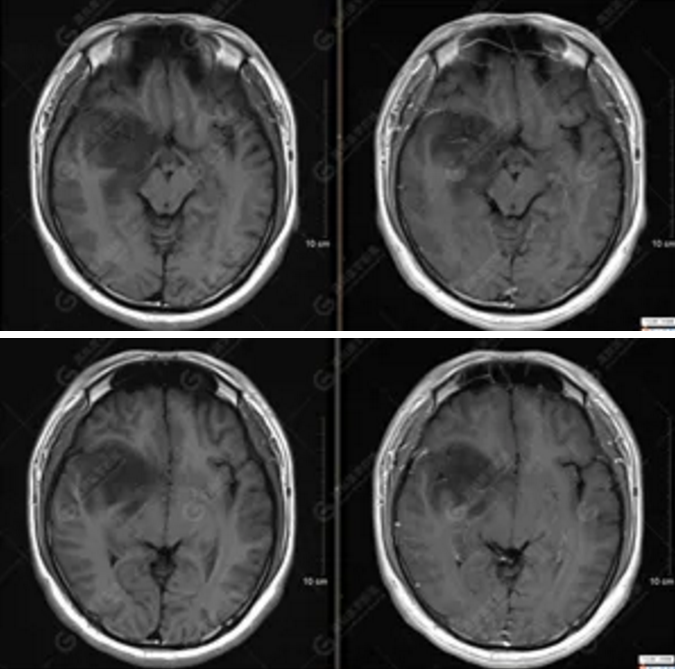

【MRI平掃及增強(qiáng)檢查所見(jiàn)】右側(cè)額顳島葉、右側(cè)海馬及右側(cè)基底節(jié)區(qū)見(jiàn)一團(tuán)塊狀異常信號(hào)影,累及右側(cè)下丘腦及視交叉,大小約5.1cm×4.5cm×4.3cm,呈長(zhǎng)T1長(zhǎng)T2信號(hào),F(xiàn)LAIR序列呈等、稍高信號(hào),DWI序列呈稍高信號(hào),ADC圖高信號(hào),增強(qiáng)后無(wú)明顯強(qiáng)化;病灶周?chē)?jiàn)片狀長(zhǎng)T1長(zhǎng)T2水腫信號(hào)影,F(xiàn)LAIR序列呈高信號(hào),病灶內(nèi)見(jiàn)右側(cè)大腦中動(dòng)脈穿行。余腦實(shí)質(zhì)內(nèi)未見(jiàn)局灶性信號(hào)異常,增強(qiáng)后未見(jiàn)異常強(qiáng)化。右側(cè)側(cè)腦室輕度受壓,余腦室、腦池大小、形態(tài)均正常,中線(xiàn)結(jié)構(gòu)居中

1.右側(cè)額顳島葉、右側(cè)海馬及右側(cè)基底節(jié)區(qū)占位病變,考慮為彌漫性星形細(xì)胞瘤可能性大,累及右側(cè)大腦中動(dòng)脈、右側(cè)下丘腦及視交叉;

彌漫性星形細(xì)胞瘤(WHO Ⅱ級(jí))。